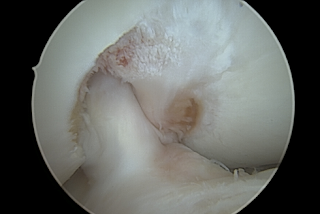

Voordat hij aan de slag ging met de notchplastiek inspecteerde hij de rest van mijn knie. Die vertoonde wat gebruikerssporen. Doordat de achterzijde van de patella ten gevolge van de strekbeperking bovengemiddelde druk heeft moeten verdragen is deze wat gerafeld geraakt. Kraakbeenschade focaal graad 1. Niet zorgelijk. Net als het kraakbeen in het mediale compartiment van het tibiaplateau. Geen reden tot zorg. Het laterale compartiment van het tibiaplateau heeft focaal graad 2 schade. Ook niet zorgwekkend.

Mijn mediale meniscus ziet er prima uit. Mijn laterale meniscus vertoont ook een rafel en de oppervlakte is niet meer zo glad. Volgens Jacco zijn dit gebruikerssporen van jarenlang intensief sporten. Enfin, geen relevante nevenschade die een terugkeer op het voetbalveld in de weg zou staan. Dat is super positief.

Beeld van arthroscopie in de knie

Binnenzijde van de knie na notchplastiek

Notchplastiek geslaagd: de kruisband ligt mooi vrij.